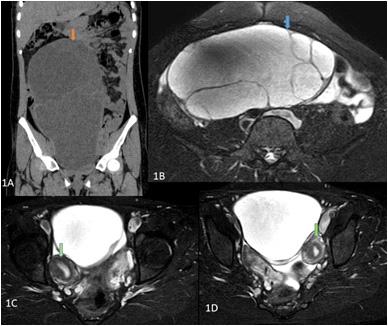

histopathology or polymerase chain reaction in a Patient with a clinical diagnosis of Invasive Mucormycosis. Cases were considered COVID-19 associated if the patient received a positive Reverse Transcription Polymerase Chain Reaction or Antigen test result for SARS-CoV-2 during the 60 days preceding the mucor diagnosis1.” Every patient is evaluated at presentation with detailed history, Clinical examination, ENT, Ophthalmic and Neurological examination to assess the extent of disease. Patients’ occupational history, personal habits, Socio-economic status (Modified B G Prasad Scale), prior treatment, vaccination status & COVID status were recorded at admission. Patients with pre-existing Facial Nerve palsy due to other known causes like cerebrovascular accident, non-covid intracranial, temporal bone, parotid pathology were excluded. Facial soft tissue involvement if mimicking Facial Palsy was also excluded. Facial Nerve function assessment was done in detail. It was first subdivided into upper and lower Motor Neuron type of deficit. LMN lesions were further graded by the House Brackmann Scoring System. Topo-diagnostic tests like Schirmer test, Stapedial reflex test and Taste sensation were assessed as far as practicable. Diagnostic Nasal Endoscopy (DNE) and Radiological assessment (Computed Tomography and Magnetic Resonance Scan of Head, Neck and Orbit) was done. Patients undergoing surgical debridement and those considered for conservative management were followed up at three months to check for change in the state of Facial Palsy. All interventions were done maintaining institutional and ICMR COVID protocol.

Radiological assessment in the form of Magnetic Resonance Imaging and Computed Tomography of the diseased site was done. Contrary to the clinical presentation, all of the patients (100%) had Nose and Para nasal sinus involvement. Orbit was involved in 72.72% of patients. Pterygopalatine fossa involvement and intracranial disease extension was found in 54.54% of the patients respectively. None of the patients had infra-temporal fossa and temporal bone involved by Mucor.

Route of disease spread was classified (based on clinico radiological findings) as Superior route if there were features of Nose and Skull Base involvement. Patients having Nose and Oral cavity involvement without involvement of the Skull base were considered as Mucor with Inferior Route of spread. It was found that 9 out of 11 patients of CAM with Facial Nerve Palsy had features suggestive of Superior route of Mucor spread.

Fig 1Fig 2Fig 3 Fig 4Fig 5

Figs 1-5 — Photographs of patients suffering from Post COVID Mucormycosis with new onset Facial Nerve Palsy